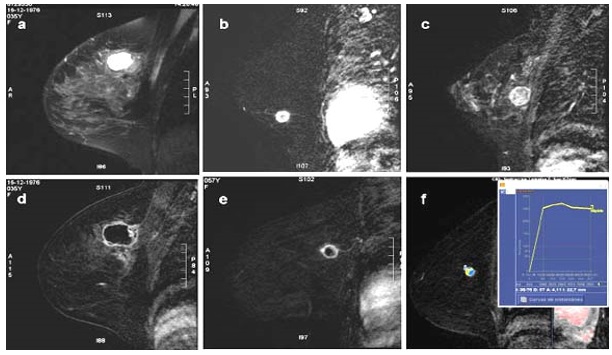

Características en RNM del CMTN

En los resultados de las características en resonancia magnética, se debe tener en cuenta que de las 17 pacientes solo se dispone información de 8 resonancias magnéticas realizadas en centros periféricos. Esto representa el 75% de la muestra, equivalente a 8 casos.

De estos casos se destaca que informan una cantidad de tejido fibroglandular tipo B, aunque no describen el realce parenquimatoso de fondo ni hallazgos asociados.

En lo que respecta a la descripción nodular, se encontró que en el 77,7% de los casos (7 de 8) el nódulo se reportó como redondeado, seguido de la forma ovalada.

Los márgenes del nódulo en 7 casos se describen como circunscritos y solo en 1 caso se reporta como espiculado.

Según lo referido realce interno del nódulo, 5 casos presentaron realce heterogéneo periférico y 3 casos mostraron un realce en forma de anillo.

Finalmente, en la evaluación de la valoración de las curvas cinéticas, se notó que en la fase inicial los 8 casos tenían una fase rápida. En la fase tardía, 6 de los casos presentaban un patrón de wash out, mientras que 2 casos mostraban un tipo de realce en meseta.

Los resultados de resonancia magnética mostraron hallazgos consistentes con la literatura, incluyendo el realce periférico, nódulos heterogéneos y curvas cinéticas tipo 2 y 3. A pesar de la limitada disponibilidad de resonancias magnéticas en centros periféricos, estos hallazgos respaldan la utilidad de esta técnica en la evaluación de tumores mamarios.

Anexo 3. Imágenes CMTN en resonancia magnética